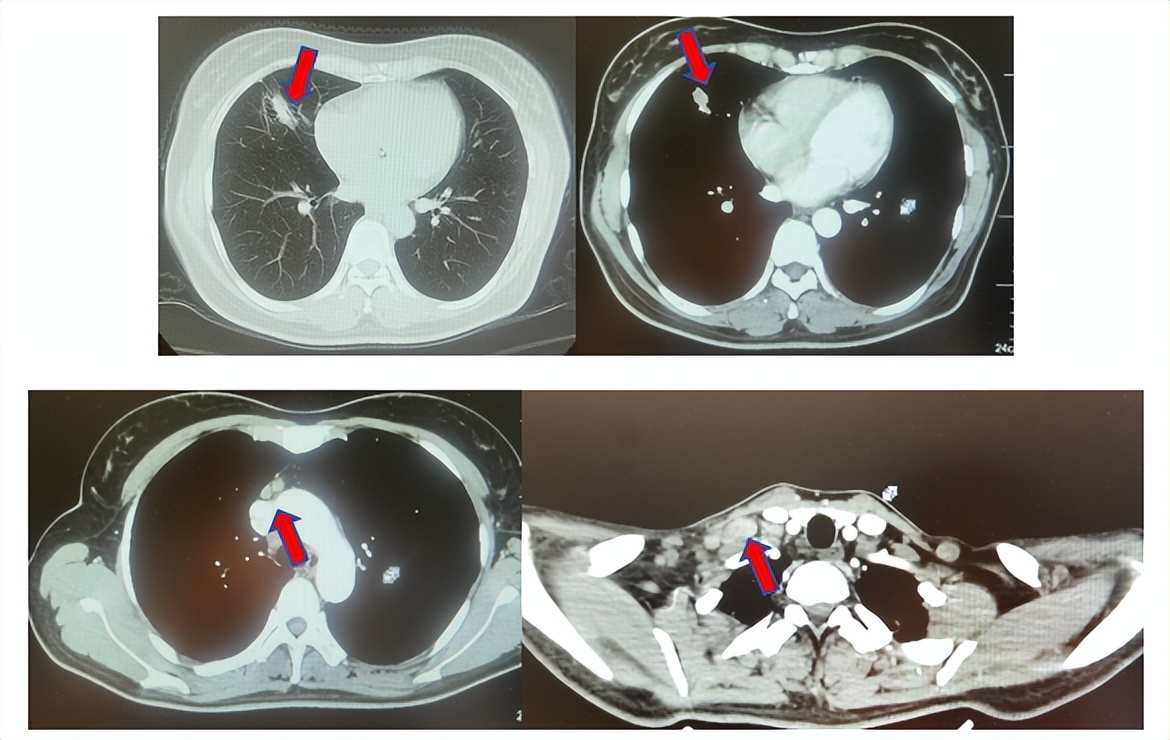

患者女性,46岁,2018年12月以“触及颈部包块1个月”为主诉入院,行肺CT提示右肺中叶占位,于外院行PET-CT:右肺中叶不规则密度增高影伴临近透光区及条索影,考虑恶性,伴右侧颈部锁骨上纵隔内及右肺门淋巴结影,代谢增高。门诊以右肺中叶占位收入院。入院查体:发育正常,营养良好,ECOG评分1分,NRS评分0分,双侧胸廓对称,右侧锁骨上可触及馋豆大淋巴结,双肺查体基本正常。患者否认肝炎、结核等传染病史,否认高血压、糖尿病史,否认外伤、手术史,否认输血史,食物、药物过敏史,否认家族性遗传病史,无吸烟、饮酒史。

2.2影像学检查(图5)

肺+全腹CT增强:右肺中叶肿块,考虑恶性,双肺胸膜下炎症,双侧胸膜局限性增厚,右侧锁骨上淋巴结增大,纵隔淋巴结稍大;

颈部CT增强:右侧锁骨上及右颈部、纵隔多发淋巴结肿大。

图5:上两图分别展示基线时肺CT肺窗及纵隔窗右肺中叶病灶影像,下两图表示基线状态时纵隔淋巴结及锁骨上淋巴结影像。

结合病理及影像学检查最终诊断:右肺中叶恶性肿瘤(腺癌,cT1N3M0 IIIB期驱动基因阴性)伴右侧肺门转移,纵隔淋巴结转移,锁骨上淋巴结及颈部淋巴结转移。

患者符合我科正在开展的一项“评估信迪利单抗或安慰剂联合培美曲塞和铂类化疗用于晚期或复发性肺鳞状细胞非小细胞肺癌一线治疗有效性和安全性的随机,双盲,III期研究(ORIENT-11)”临床研究入组条件,应用信迪利单抗或安慰剂联合培美曲塞+卡铂治疗4周期,信迪利单抗或安慰剂联合培美曲塞维持治疗13周期,后应用信迪利单抗或安慰剂应用至2年。试验结束后出组,揭盲患者为信迪利治疗组。治疗期间最佳疗效肺内病灶近CR(图6)。停药后每3个月-6个月复查随访,未见肿瘤复发转移征象(图6),截止至目前为止,一线无进展生存已超过75个月。

图6:上三图分别展示2019年6月患者达到最佳疗效时肺CT肺窗及纵隔窗右肺中叶病灶及锁骨上淋巴结影像,下两图表示2025年2月患者最近复查评效时肺CT肺窗及纵隔窗肺内病灶影像